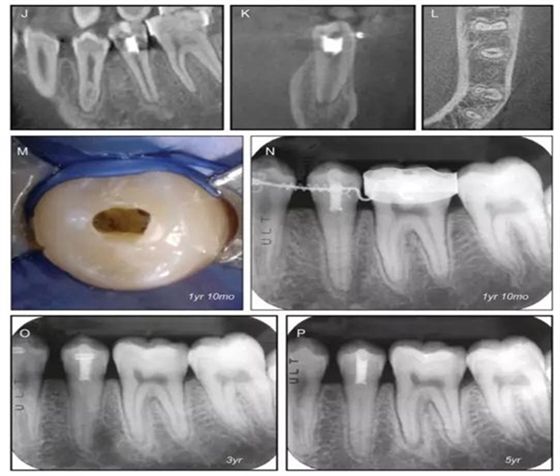

原則上年輕恒牙的牙髓治療應(yīng)盡可能以保存活髓的方式以便不影響牙根繼續(xù)發(fā)育。本文3個病例均描述了根尖尚未發(fā)育完成的下頜前磨牙被確診為牙髓壞死伴有大面積根尖病損,治療過程中在根管內(nèi)發(fā)現(xiàn)了部分活髓,而采用活髓切斷后都取得了很好的療效。